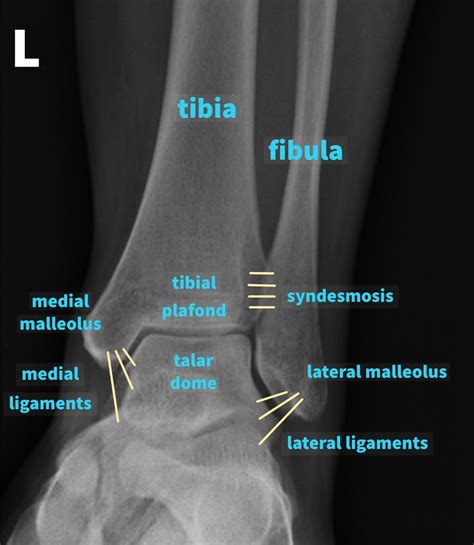

Interpreting a Normal Foot X Ray involves a thorough examination of the images to ensure that all structures appear normal. Key areas of focus include:

Bones

The bones of the foot, including the tarsals, metatarsals, and phalanges, should be clearly visible and aligned properly. Any fractures, dislocations, or deformities would be immediately apparent.

Joints

The joints between the bones should be smooth and well-defined. Any signs of arthritis, such as bone spurs or joint space narrowing, would indicate an abnormality.